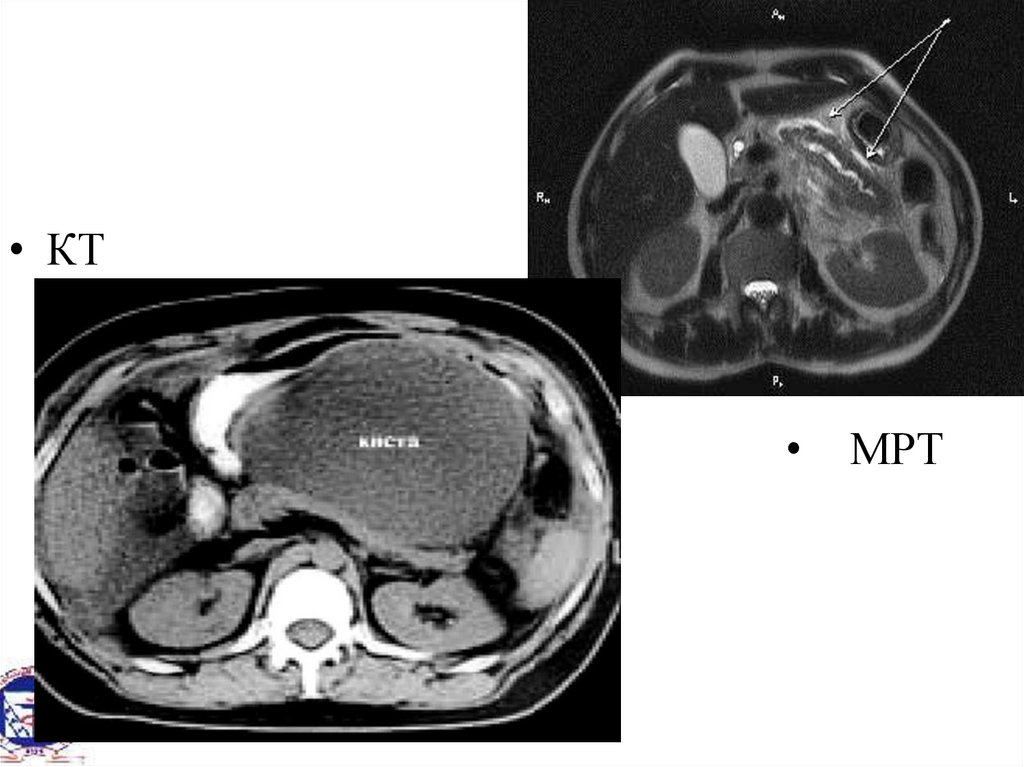

• КТ

МРТ